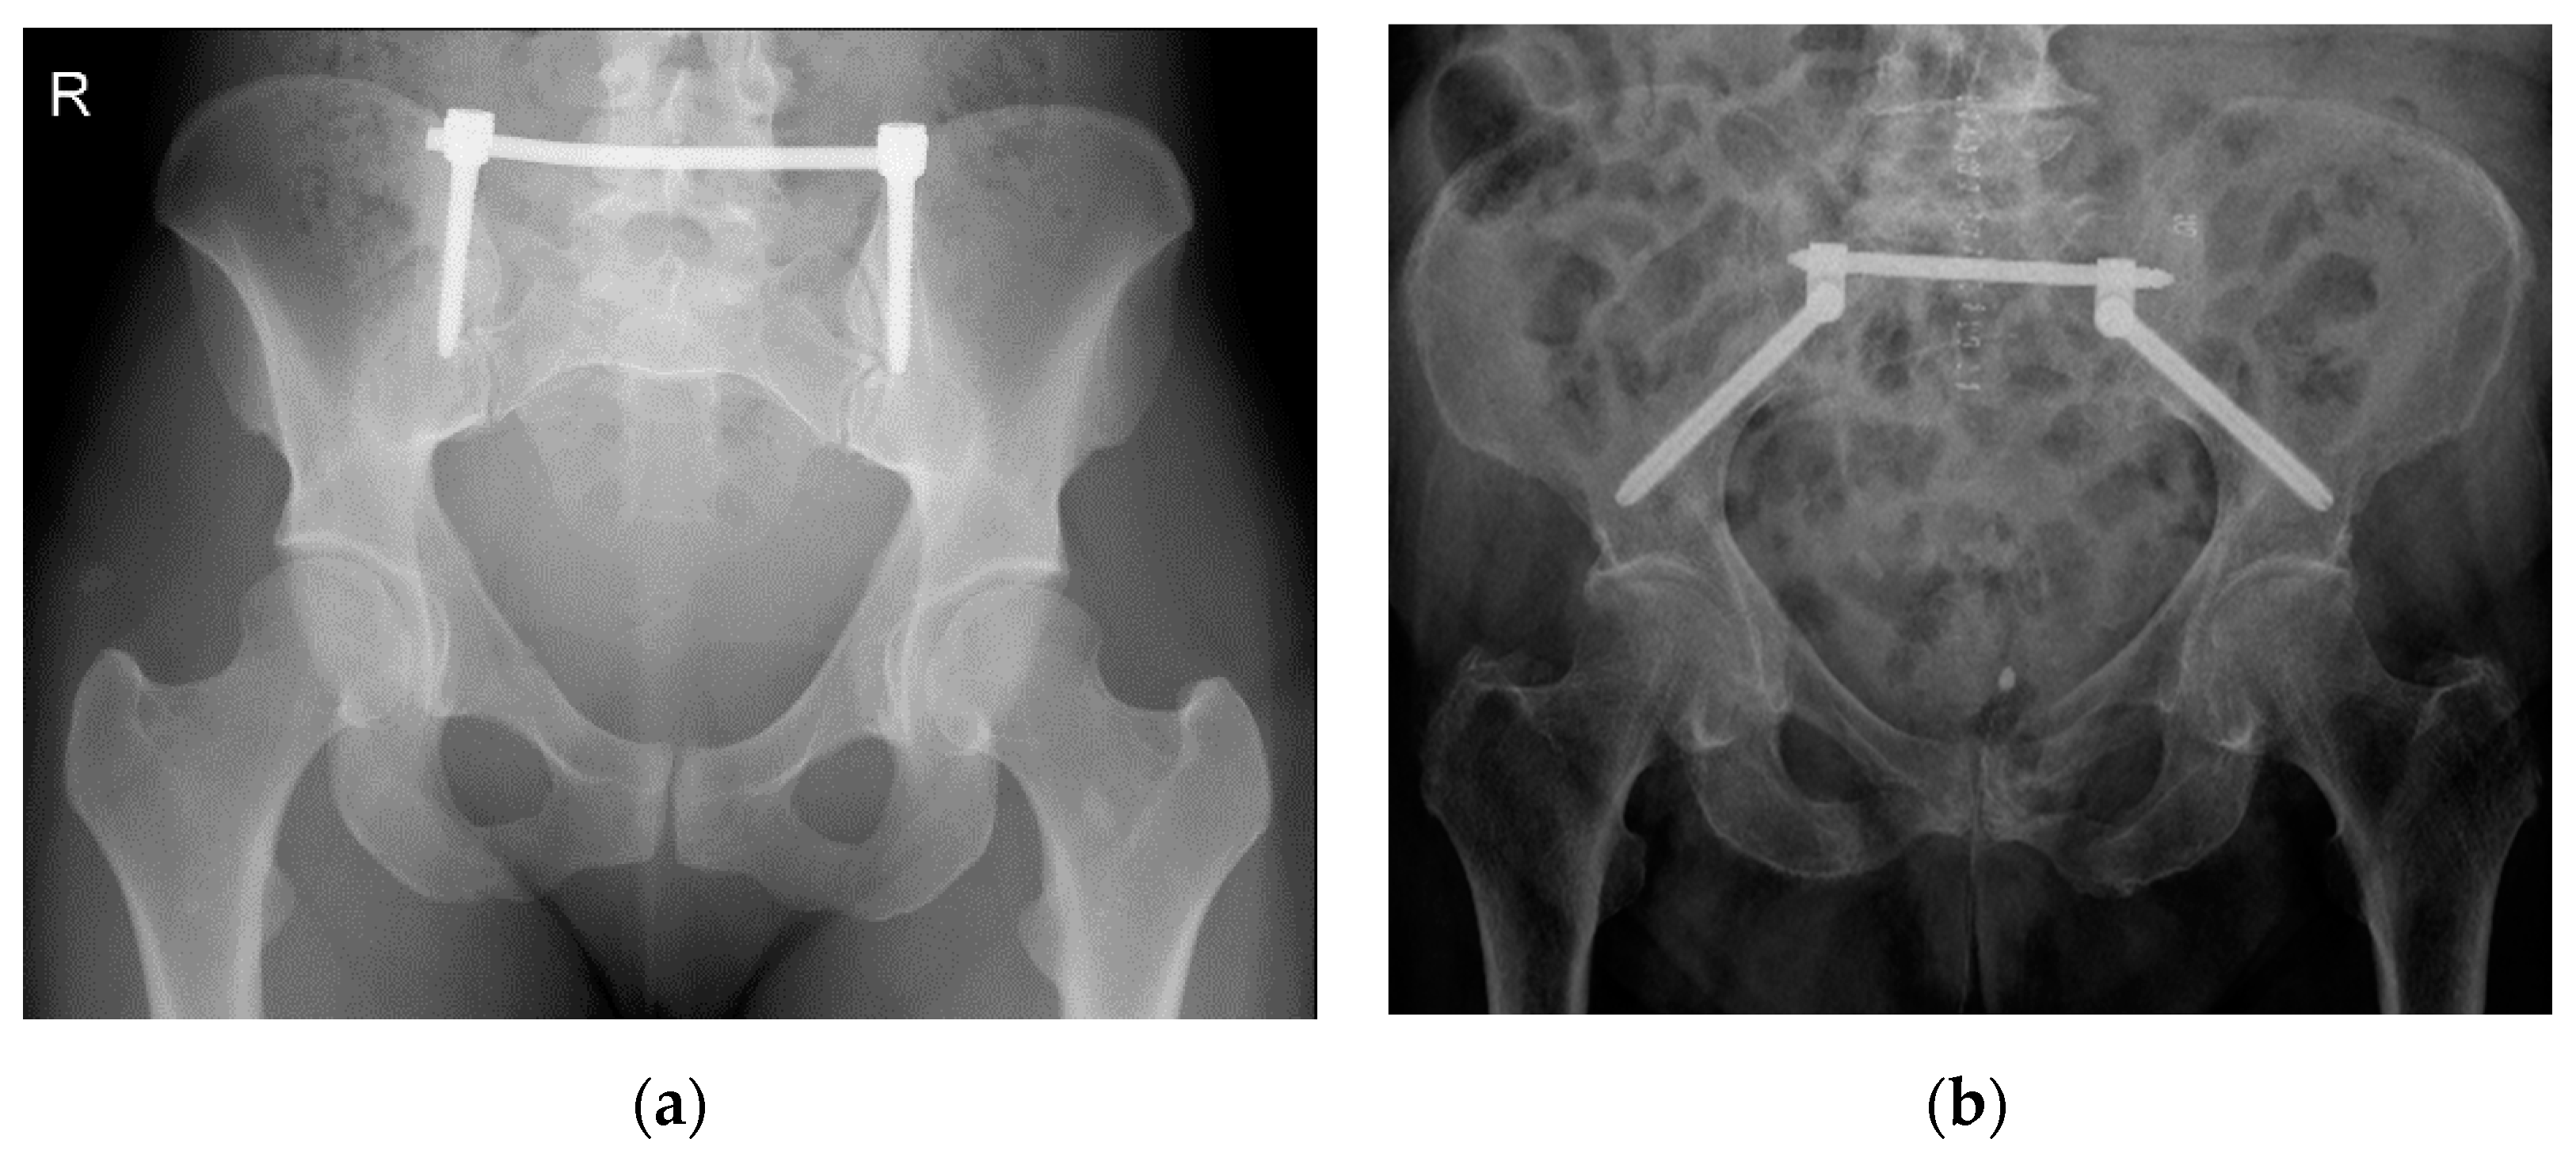

A minimally invasive procedure to stabilize an unstable posterior pelvic ring fracture is the transiliac internal fixation using an internal screw-rod system [9,10] (Figure 1). As described by Füchtmeier et al., a longitudinal incision of the skin and the fascia is performed 1 cm lateral and 2 cm above the posterior superior iliac spine. After that, the iliac crest is perforated by a pedicle finder and an ilium screw with a diameter of 7 mm and a length of up to 60 mm can be inserted in cranio-caudal direction parallel to the posterior gluteal line [9].

To account for the increasing amount of fragility fractures of the pelvis [11], Schmitz et al. modified this procedure [10] by inserting the screws at the posterior inferior iliac spine and heading towards the anterior inferior iliac spine. As a result, a screw with a length of up to 140 mm and a diameter of 8 mm can be achieved [12]. It is recommended to insert the screws under intraoperative fluoroscopic control using obturator oblique–outlet and standard lateral pelvic views [10,11,12]. After correct placement of the ilium screws, a transverse rod is inserted in a minimally invasive manner below the fascia of the spinal muscles connecting the ilium screws to each other. This way, the broken fragments of the posterior pelvic ring are merged by an angular stable implant [10].

Figure 1. X-ray of a transiliac internal fixator (TIFI)-osteosynthesis in cranio-caudal (a) and dorso-ventral (b) orientation.